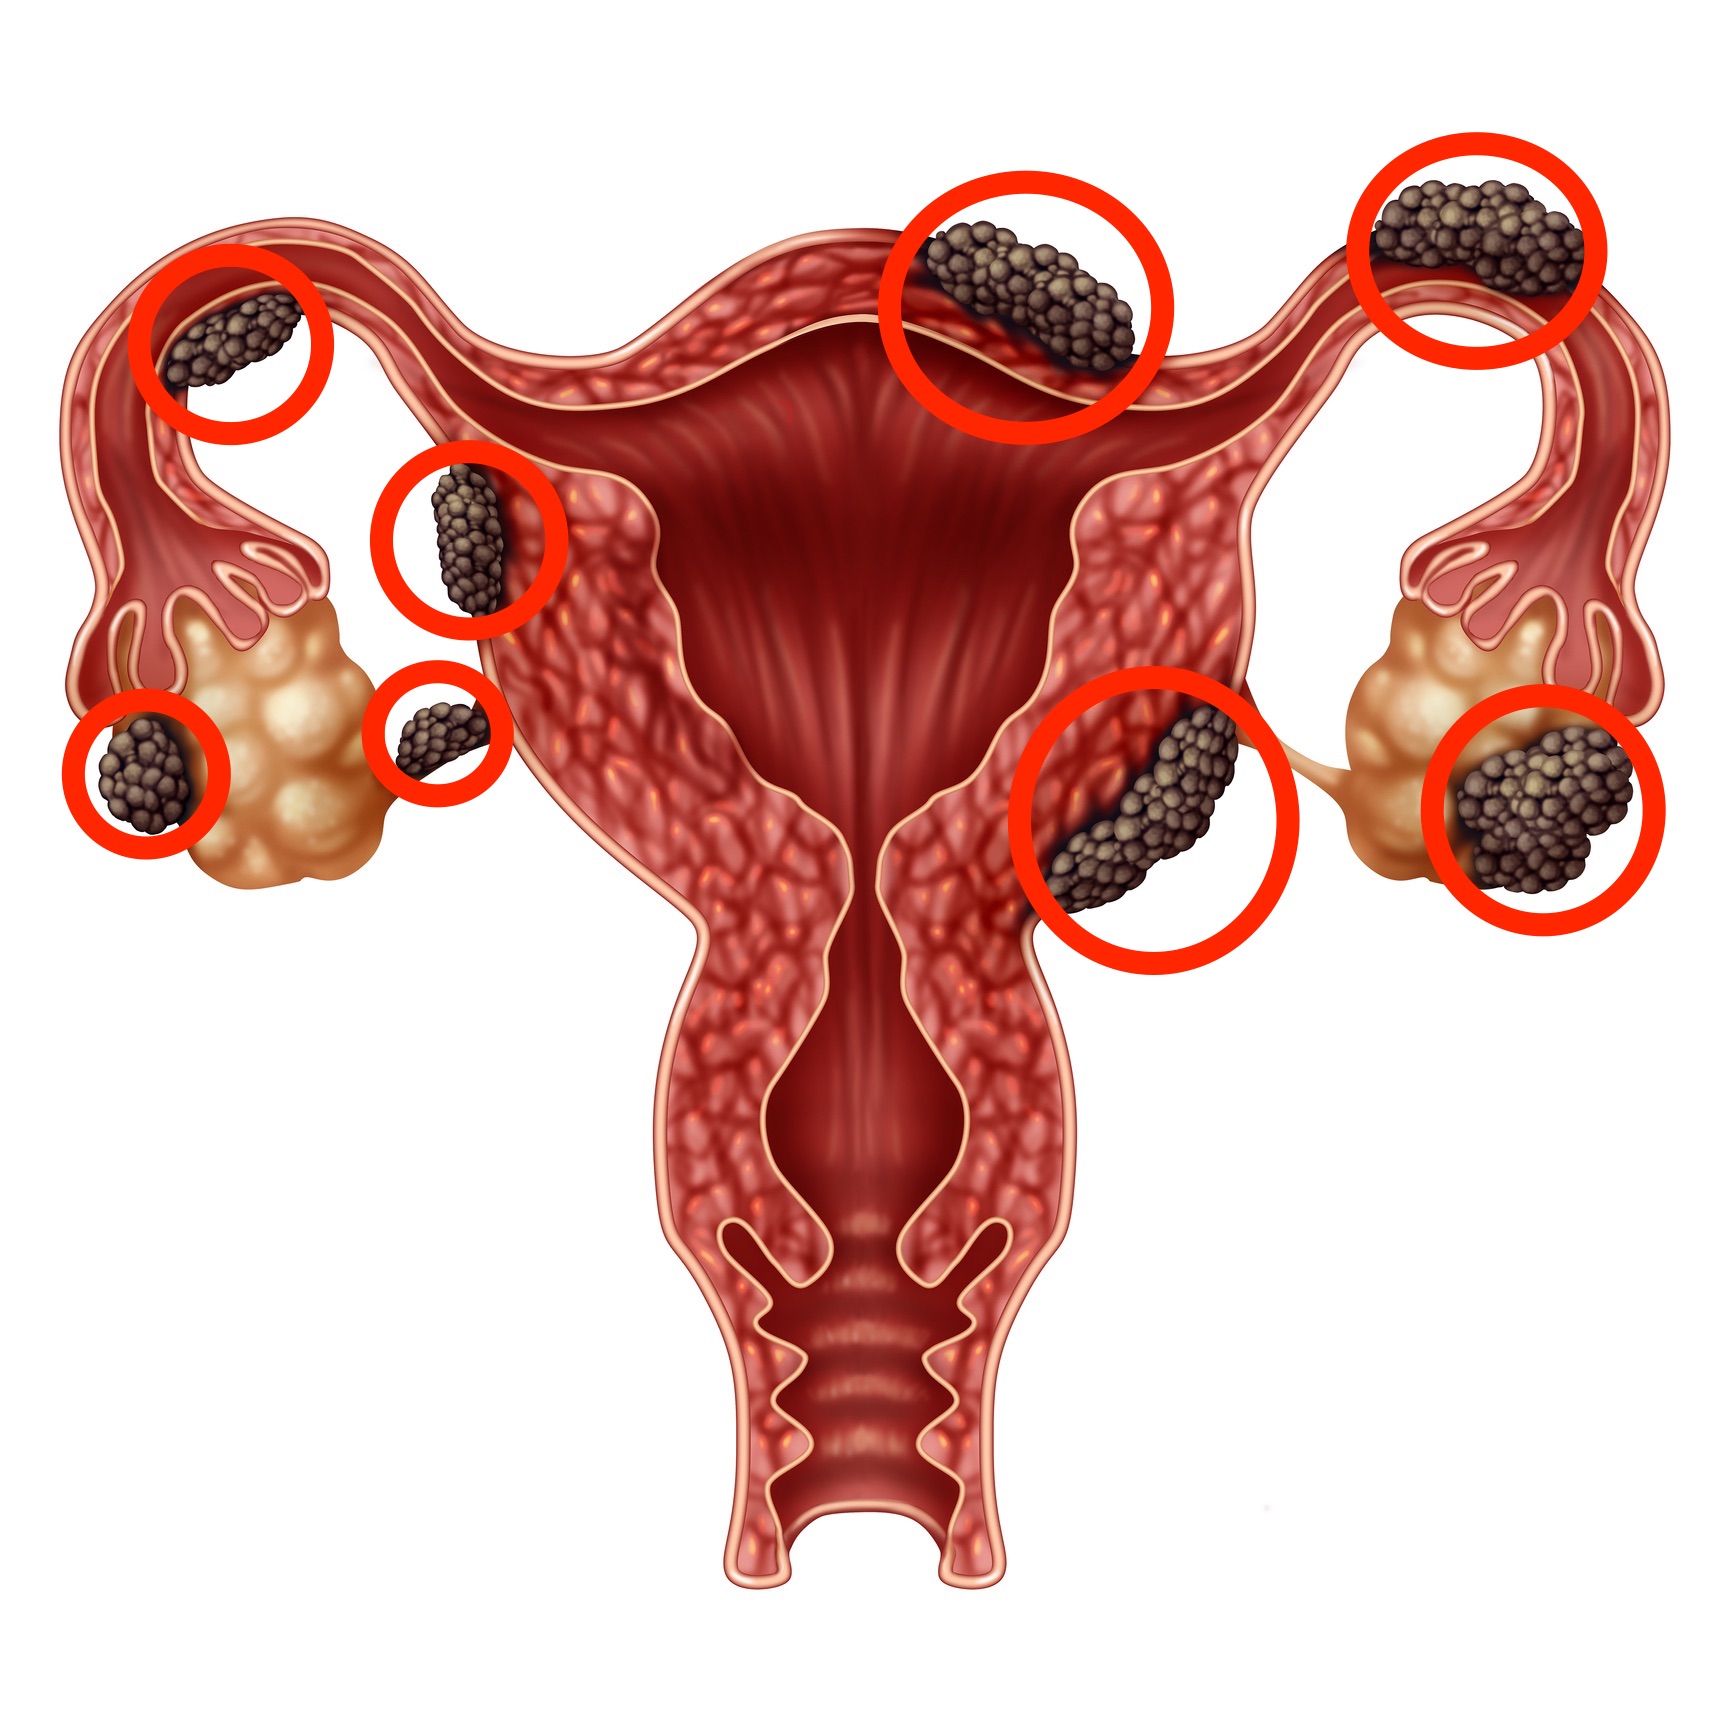

Анатомия женского организма: строение и функции матки